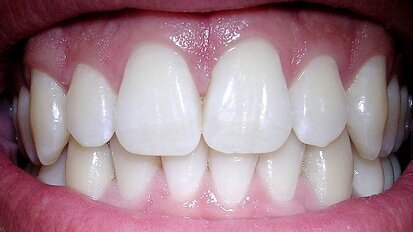

Istraživanje pokazuje da je preosetljivost dentina najzastupljenija kod mladih žena

Sijetl, Vašington, SAD: Novom studijom poprečnog preseka sprovedenom na uzorku od skoro osamsto odraslih Amerikanaca utvrđeno je da gotovo osmina ...